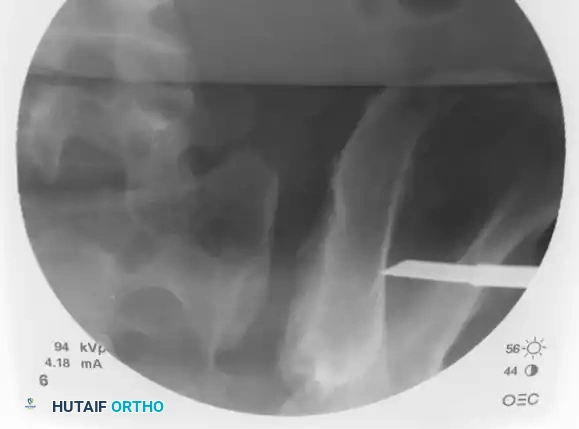

With the guidewire safely positioned in the S1 body (or extending into the contralateral S1 body if a trans-sacral screw is planned), measure the required screw length using a cannulated depth gauge.

Image

Advance the appropriate cannulated drill bit over the guidewire. Drill through the outer iliac cortex and across the sacroiliac joint. In young patients with dense bone, drilling into the sacral body may be necessary; in osteoporotic patients, drilling only the lateral iliac cortex is often sufficient to prevent stripping the sacral cancellous bone.